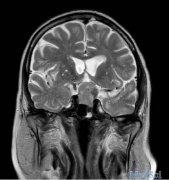

患者男,85岁,因头痛、呕吐、双眼进行性视力丧失5天就诊。否认体重下降、惊厥、肢体或面部不适等。有高血压、腹主动脉瘤、甲状腺功能减退和良性前列腺肥大。胶质瘤...